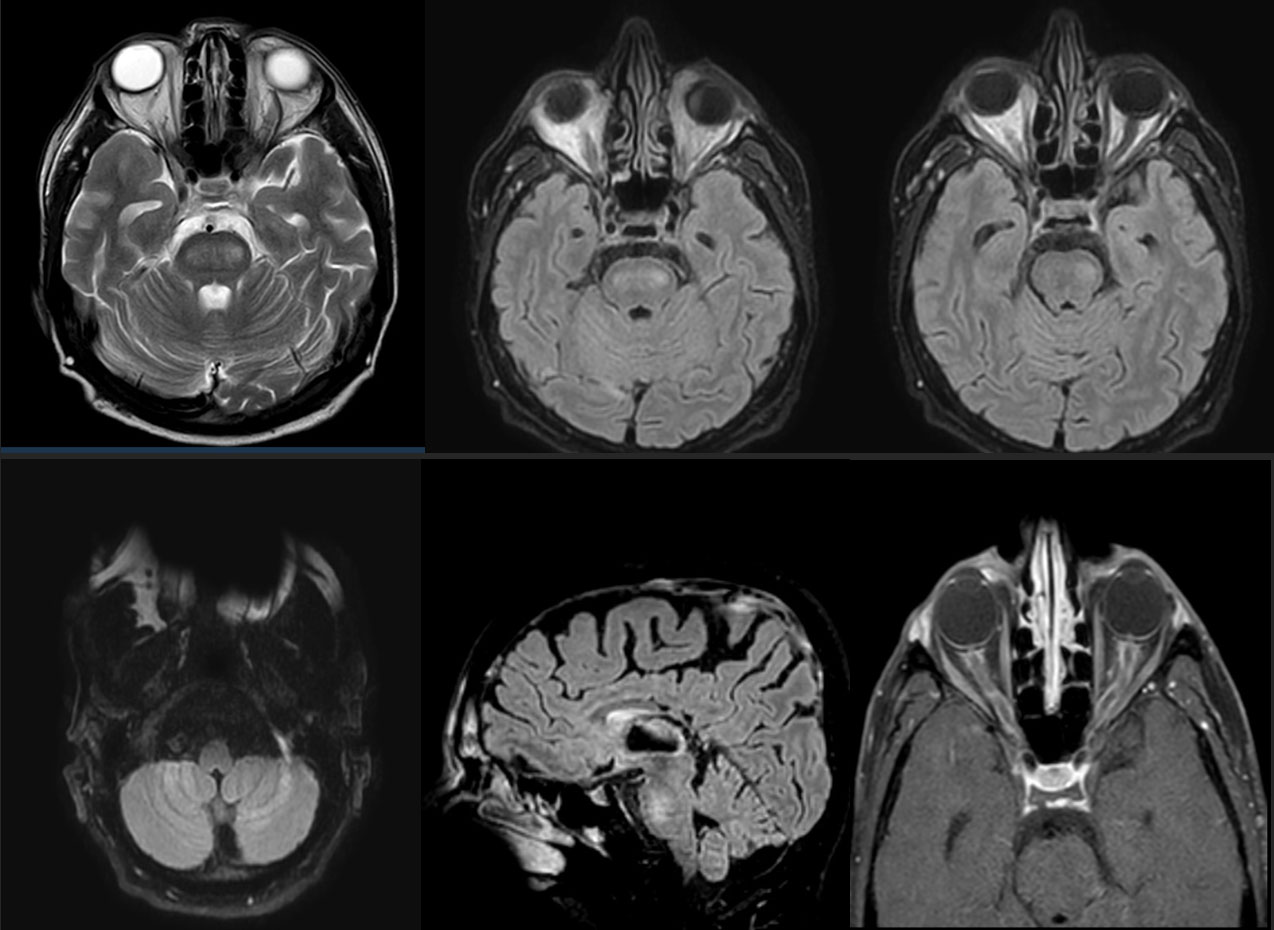

Los paraclínicos iniciales no mostraron anormalidades hematológicas ni hidroelectrolíticas. La función renal, hepática y el perfil de infecciosas y autoinmunidad fueron negativos, anticuerpos anti-AQP4 y anti-MOG negativos, estudio de LCR de características inflamatorias con proteinorraquia de 100 mg/dl y pleocitosis de 29 células con predominio mononuclear, estudios adicionales de LCR de citología, citometría y perfil infeccioso negativo. La resonancia cerebral mostró perineuritis óptica con edema de disco bilateral, lesiones hiperintensas en T2 y FLAIR en protuberancia y ambos hemisferios cerebelosos. (Figura 1). Posteriormente se confirma síndrome paraneoplásico anti-Ma2 con resultado de panel de 12 antígenos por inmunoblot de síndromes neurológicos paraneoplásicos que mostró anti-Ma2 positivo alto. Se reinició quimioterapia sistémica, con buena tolerancia.

Figura 1. A. RMN cerebral axial T2: Lesión hiperintensa en protuberancia B,C,D. RMN cerebral axial FLAIR: Lesiones hiperintensas en protuberancia y ambos hemisferios cerebelosos E. RMN cerebral sagital FLAIR: Lesión hiperintensa en protuberancia F. RMN órbitas axial T1 con gadolinio: Perineuritis con edema de disco óptico bilateral.